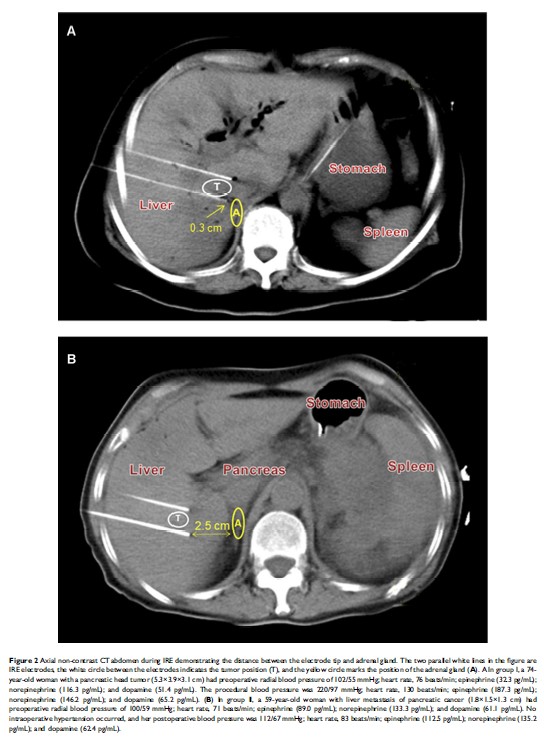

基于与肾上腺的距离,预防不可逆性电穿孔消融肝和胰腺肿瘤时的术中高血压